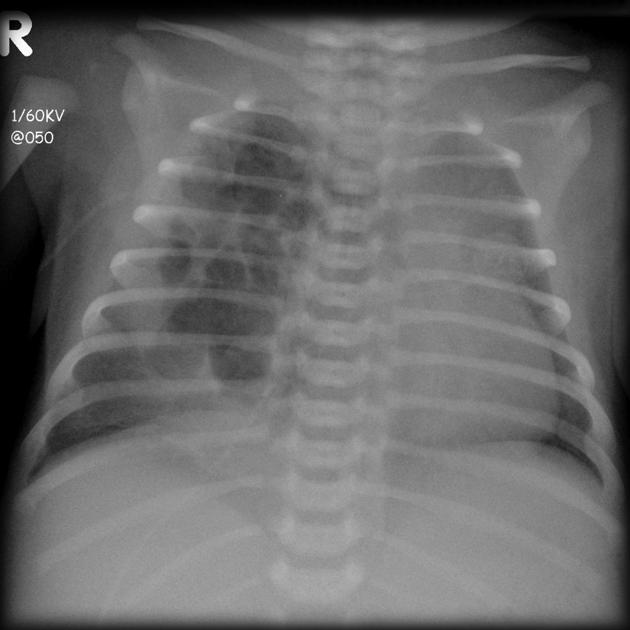

Xray findings of viral bronchitis?

Vs. pneumonia?

Hyperinflation with patchy atalectasis (esp perihilar) and interstitial opacities. Most common pathogens - rhinovirus, RSV, parainfluenza virus.

Pneumonia typically more focal airspace disease, more likely to have pleural effusion.